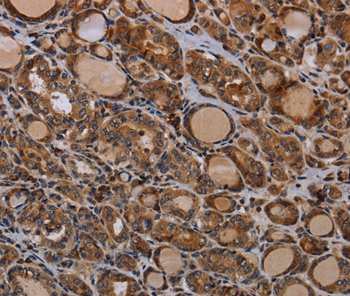

Immunohistochemical analysis of paraffin-embedded Human thyroid cancer tissue using #37794 at dilution 1/50.